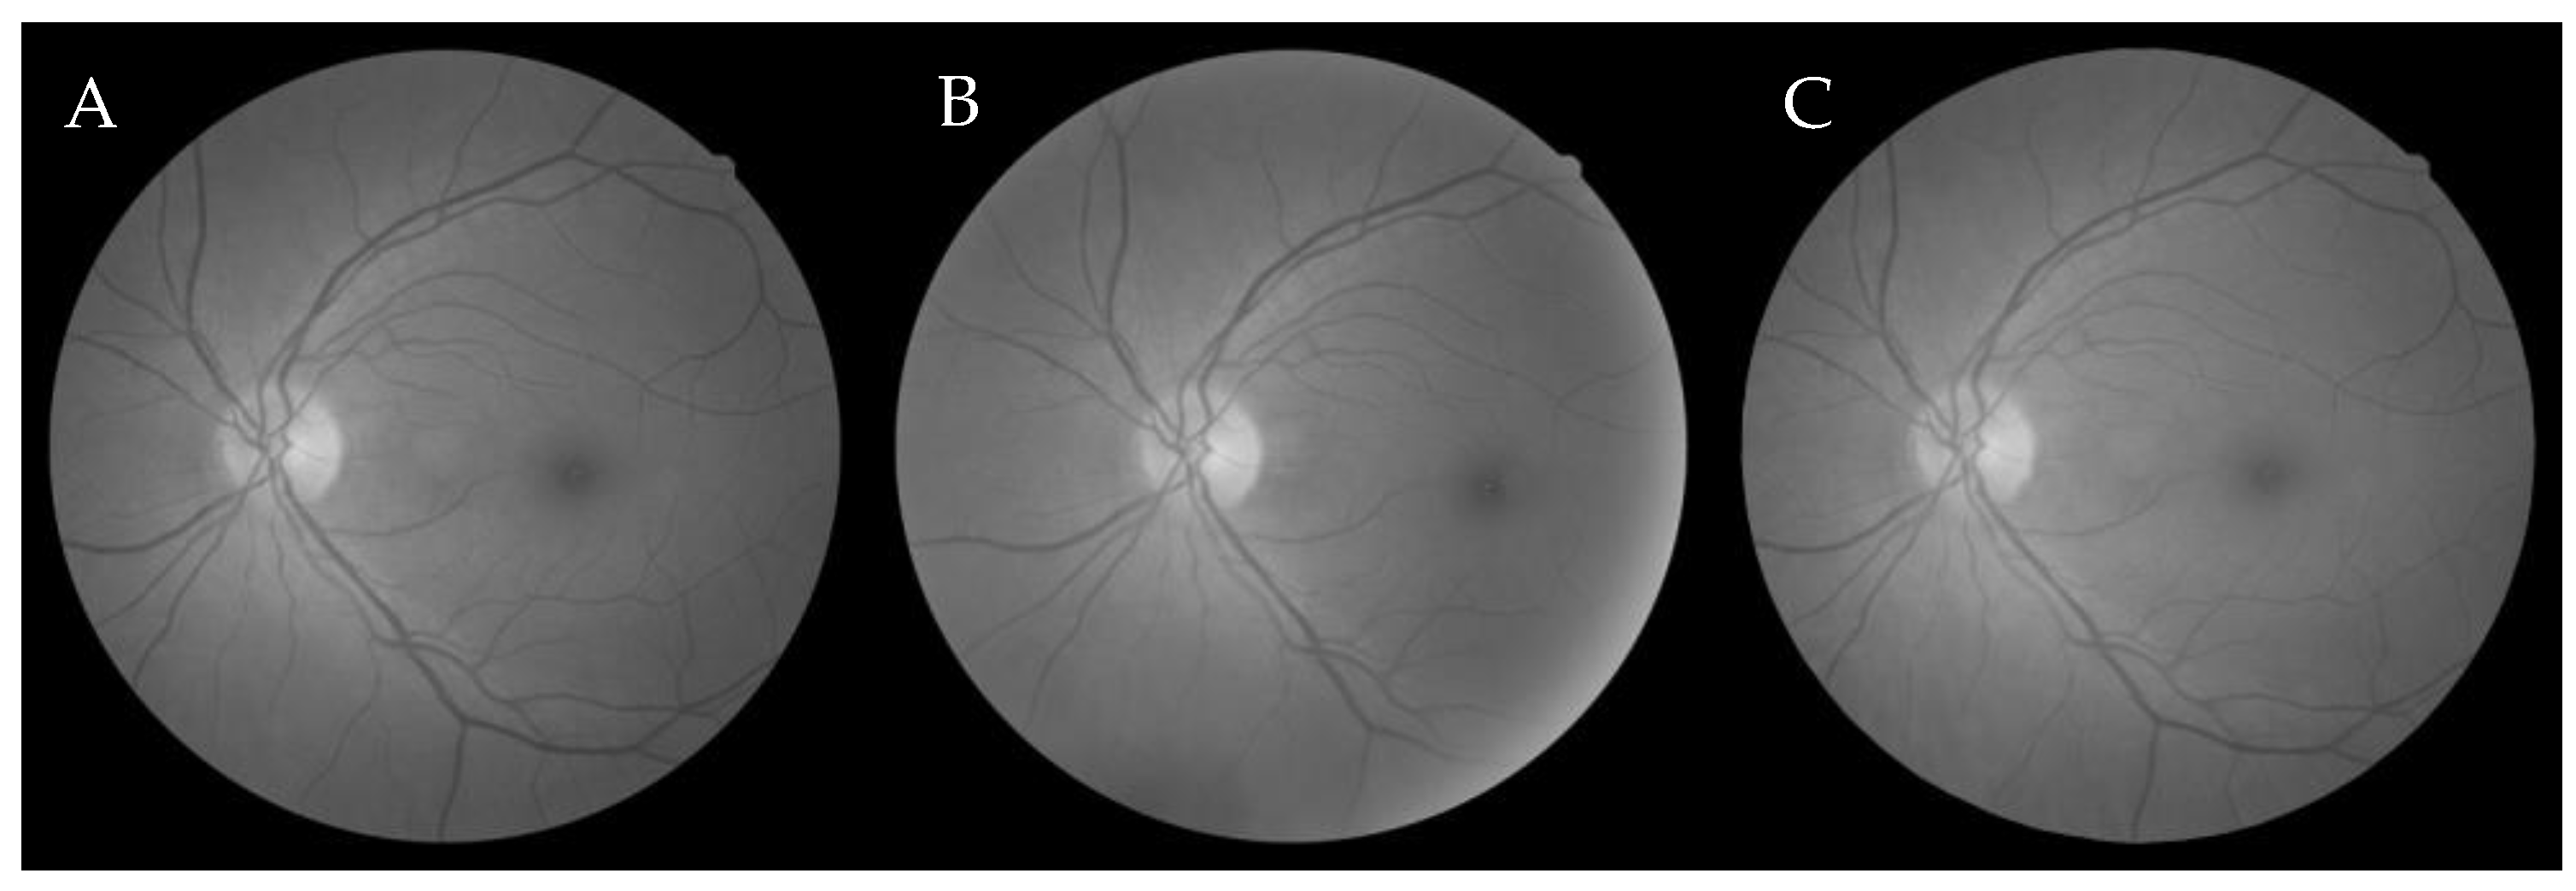

6.2.2. Firefly Algorithm-Based Wang’s Demons Registration